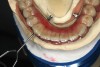

Steps for the provisional prosthetic protocol are as follows: Open-tray multi-unit impression copings are placed onto the multi-unit abutments, and the copings splinted with a low-shrinkage autopolymerizing resin (the authors prefer GC Pattern Resin™ [GC America Inc., www.gcamerica.com]) and wire bars (Figure 5) to improve the accuracy of the impression in order to attain passive fit of the restoration. An open-tray impression with a rigid vinyl polysiloxane (VPS) material is created to capture the positions of the implants and the soft tissues. This will allow the dental laboratory to construct a provisional all-acrylic resin prosthesis (Figure 6) that can be issued to the patient. An alternate method is to convert the pre-completed new or a well-fitting existing denture by picking up the implants in the mouth and refining the prosthesis extraorally. The provisional prosthesis should be carefully assessed for correct fit, esthetics, and function. If all is correct, then the provisional prosthesis is tightened to 15 Ncm. The occlusion then is carefully adjusted so that there are contacts only in the intercanine region and no premature contacts posteriorly.11,12 At this point, the patient is given strict instructions on oral hygiene with a chlorhexidine mouthwash as well as a soft-diet protocol for a period of 6 weeks to minimize micromotion.

Fig 5. Impression-taking with splinted impression copings with autopolymerizing resin and wire.

Figure 5

Fig 6. All-acrylic provisional prosthesis on the temporary cylinders.

Figure 6